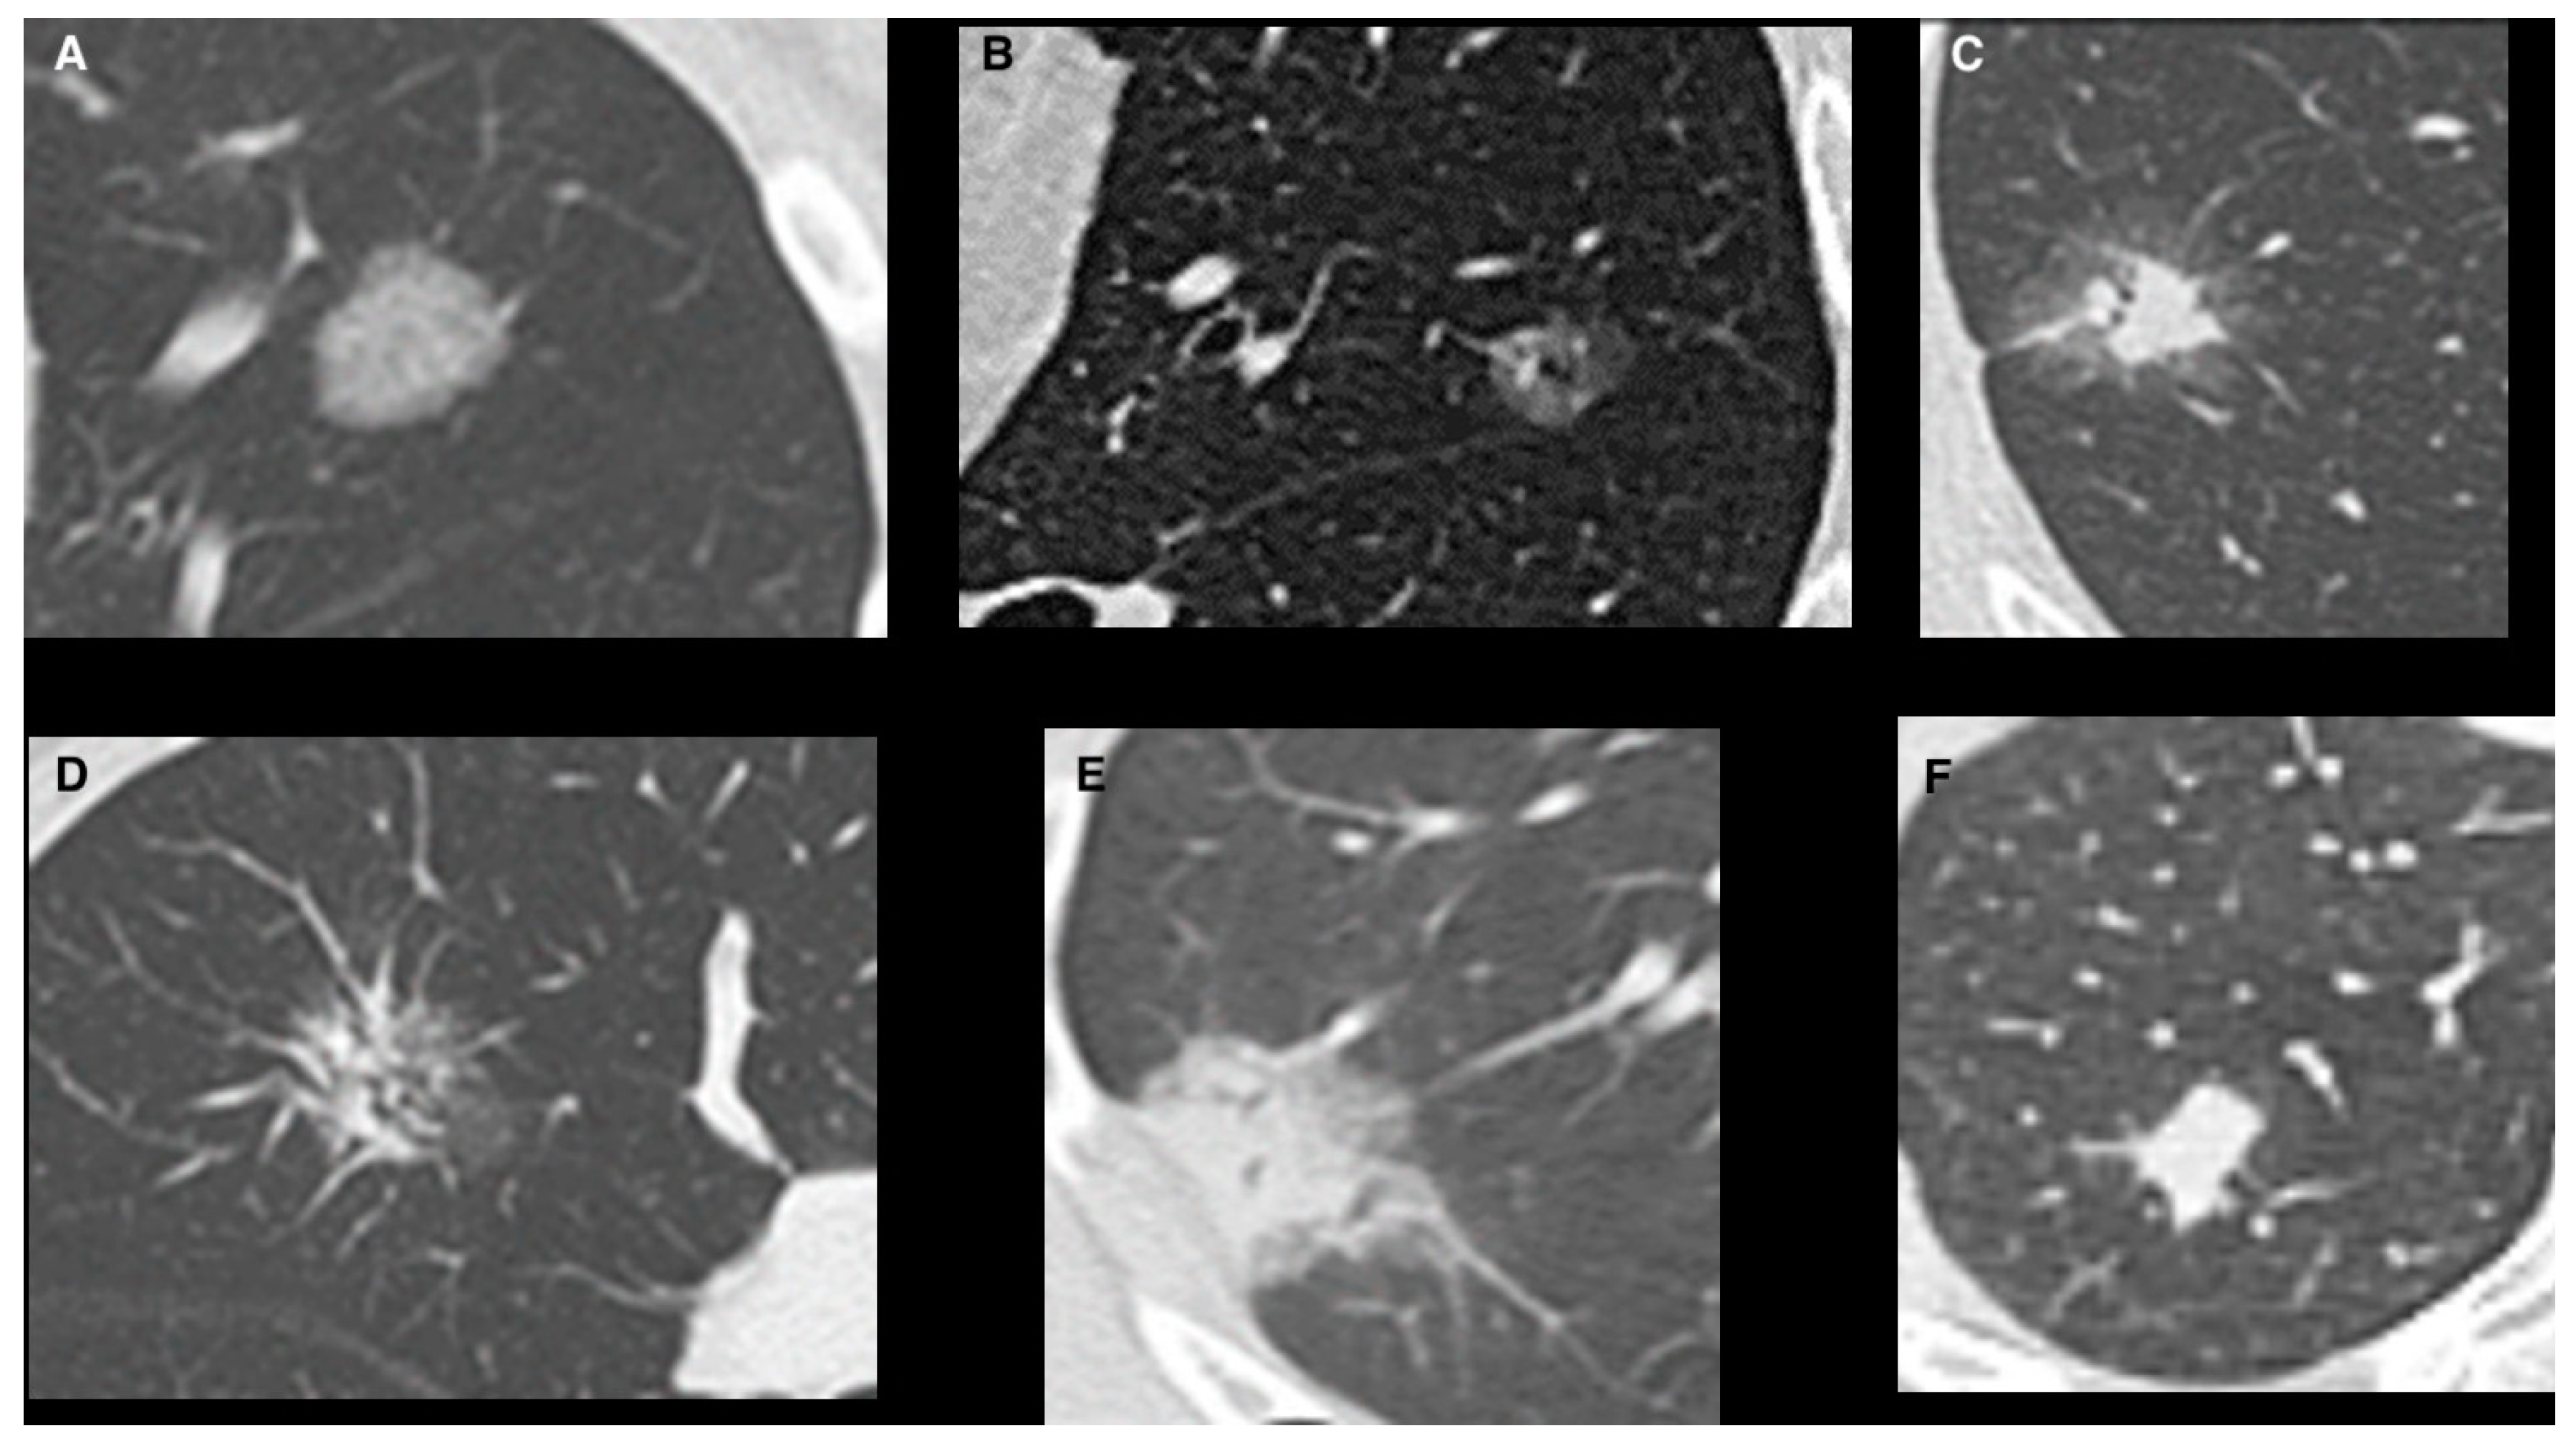

| Pure GGO, n (%) | 162 (42%) | 108 (67%) | 54 (24%) | <0.0001 |

| Pure GGO | 3.3 | 2.9–4.5 | 0.01 |

| Pure GGO | 2.3 | 2.8–4.8 | 0.003 |